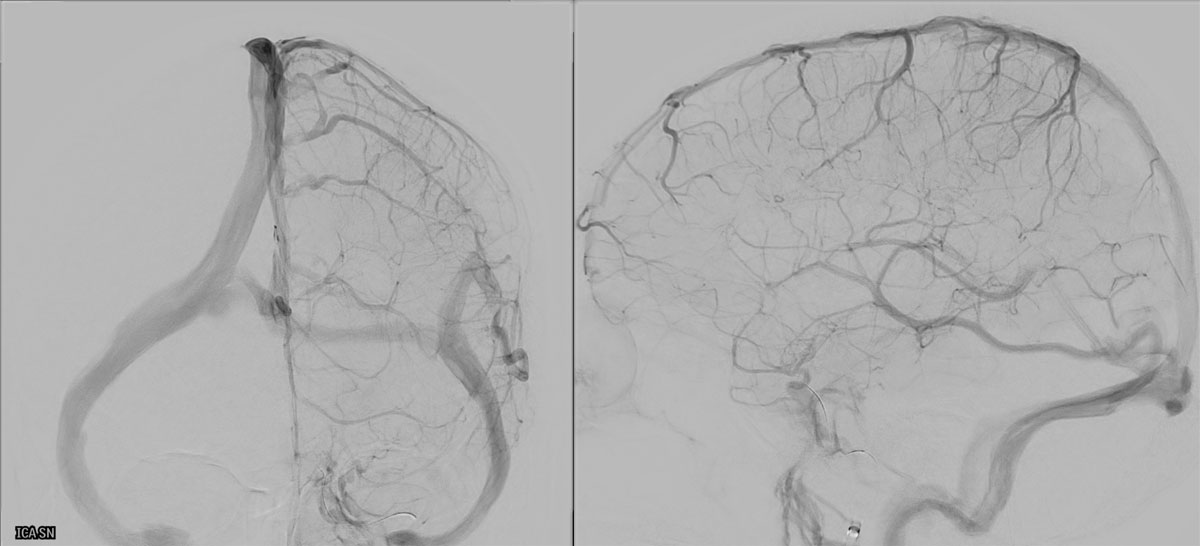

ICA-M1 intracranial dissection EVT

This clinical case presents a 28-year-old female patient presenting with a wake-up stroke, managed with endovascular treatment.

DSA

L - ICA

• BOBBY™ Balloon Guide Catheter

• Select-Sim

EVT Strategy

• Inflate the balloon, in order to dilate the true lumen

• MCA access with the softest system possible

• Open a stentriever for 20 mins with antiplatelet infusion

• Resheath the stentriever, check patency, if not stent-deployment

Headway™ DUO 156cm / Traxcess™ 14

CatchViewMini20

pEGASUS 4x20mm